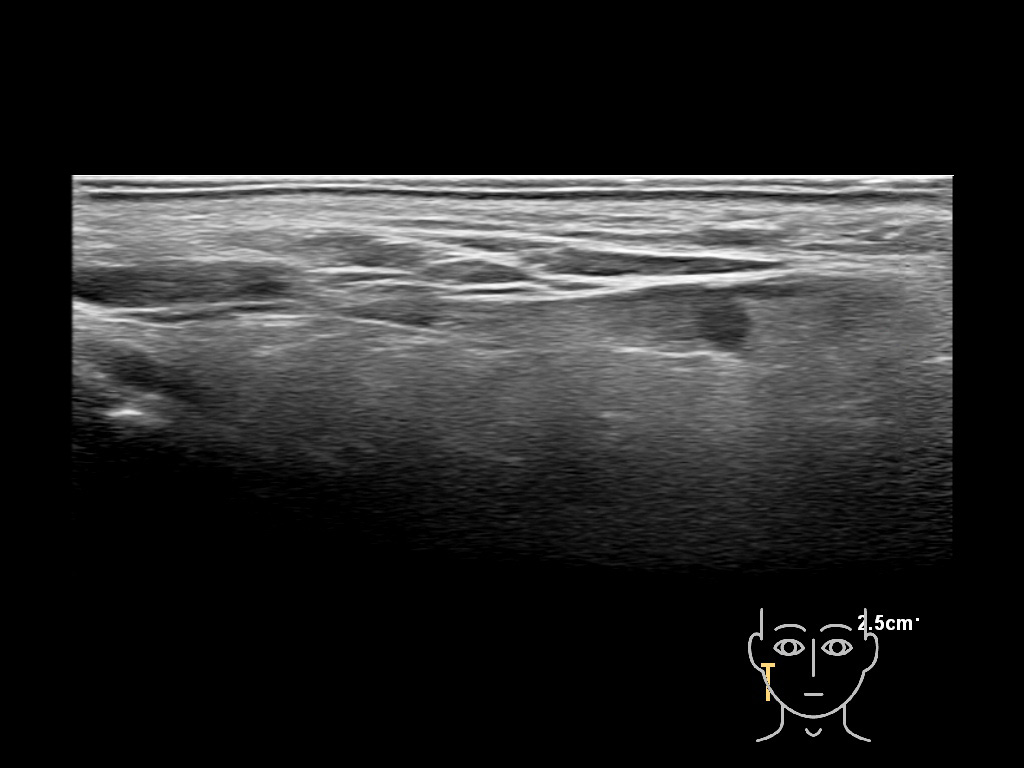

Filler injections in the parotid gland may go unnoticed, however, inflammatory reactions and abscesses may occur. Hypervascularity can be seen with color doppler. Filler deposits are supposed to be injected into the superficial fatty layer . The space to inject into this layer may be limited. Routinely we measure a width of 2-4 millimeters with sometimes subcutaneous layers being less than one millimeter thick.

Study the first image to recognize the different layers. If you are sure about the layers, swipe to the second image to view the answer (if applicable).

Hover over an image to view the secondary image or click on the image title for more information.